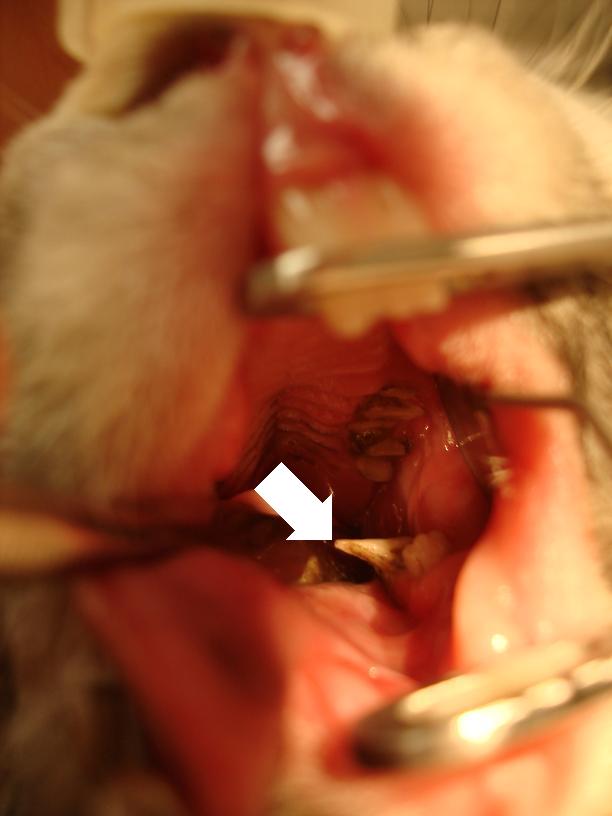

Na následujících fotografiích je zobrazen předchozí případ po zbroušení zubů zubařskou frézou na našem pracovišti.

Zákrok Zákrok